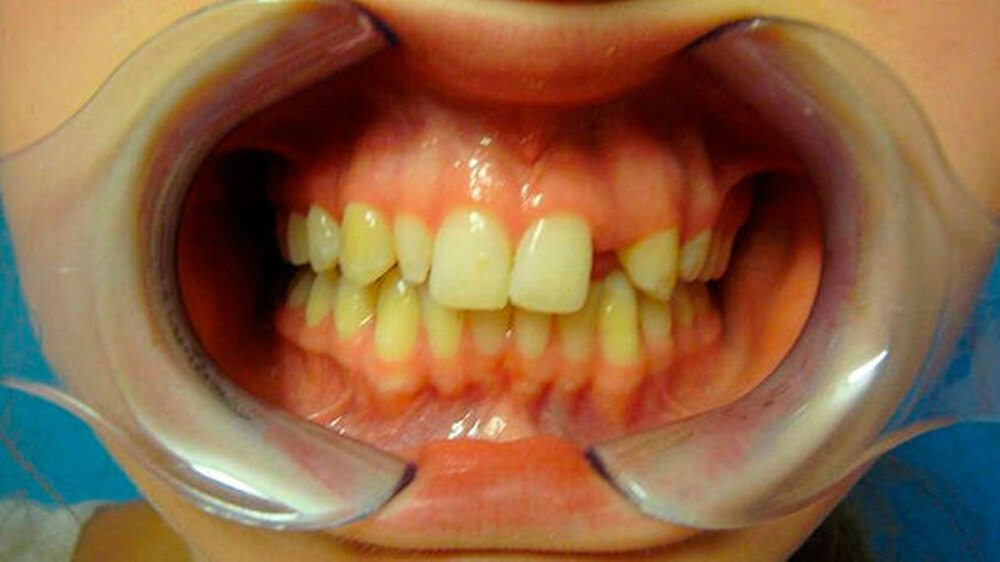

Eine 20-jährige Patientin stellte sich erstmalig zur Implantat- und Distraktionsberatung in unserer Abteilung für Mund-, Kiefer- und Gesichtschirurgie vor. Diagnostisch lagen eine mandibuläre Retrognathie, retinierte und verlagerte Zähne 18, 28, 38 und 48, ein Zapfenzahn 12, ein fehlender Zahn in regio 022, eine Mittellinienverschiebung und ein Engstand der Oberkieferfront vor (Abbildungen 1a bis d). Im Rahmen der klinischen Untersuchung und basierend auf dem Auswertungsergebnis der Digitalen Volumentomografie (DVT) führten wir bei der Patientin im Hinblick möglicher therapeutischer Maßnahmen eine differenzial-therapeutische Beratung durch.

Klinisch als auch radiologisch lag eine konvergierende Wurzelstellung der Zähne 21 und 23 vor. Eine unkomplizierte implantatprothetische Versorgung der Lücke 022, das heißt ohne Verletzung der benachbarten angulierten Zähne, erschien nicht möglich. Die Schwierigkeit bestand darin, die Lücke 022 durch körperliche Bewegung der Zähne zu öffnen, was sich bislang mittels festsitzender Apparatur als frustran erwiesen hatte. Der Patientin wurde aufgrund der vorliegenden Diagnose eine parodontal akzelerierte osteogenetische Orthodontie (PAOO) im Bereich des linken Oberkiefers empfohlen.